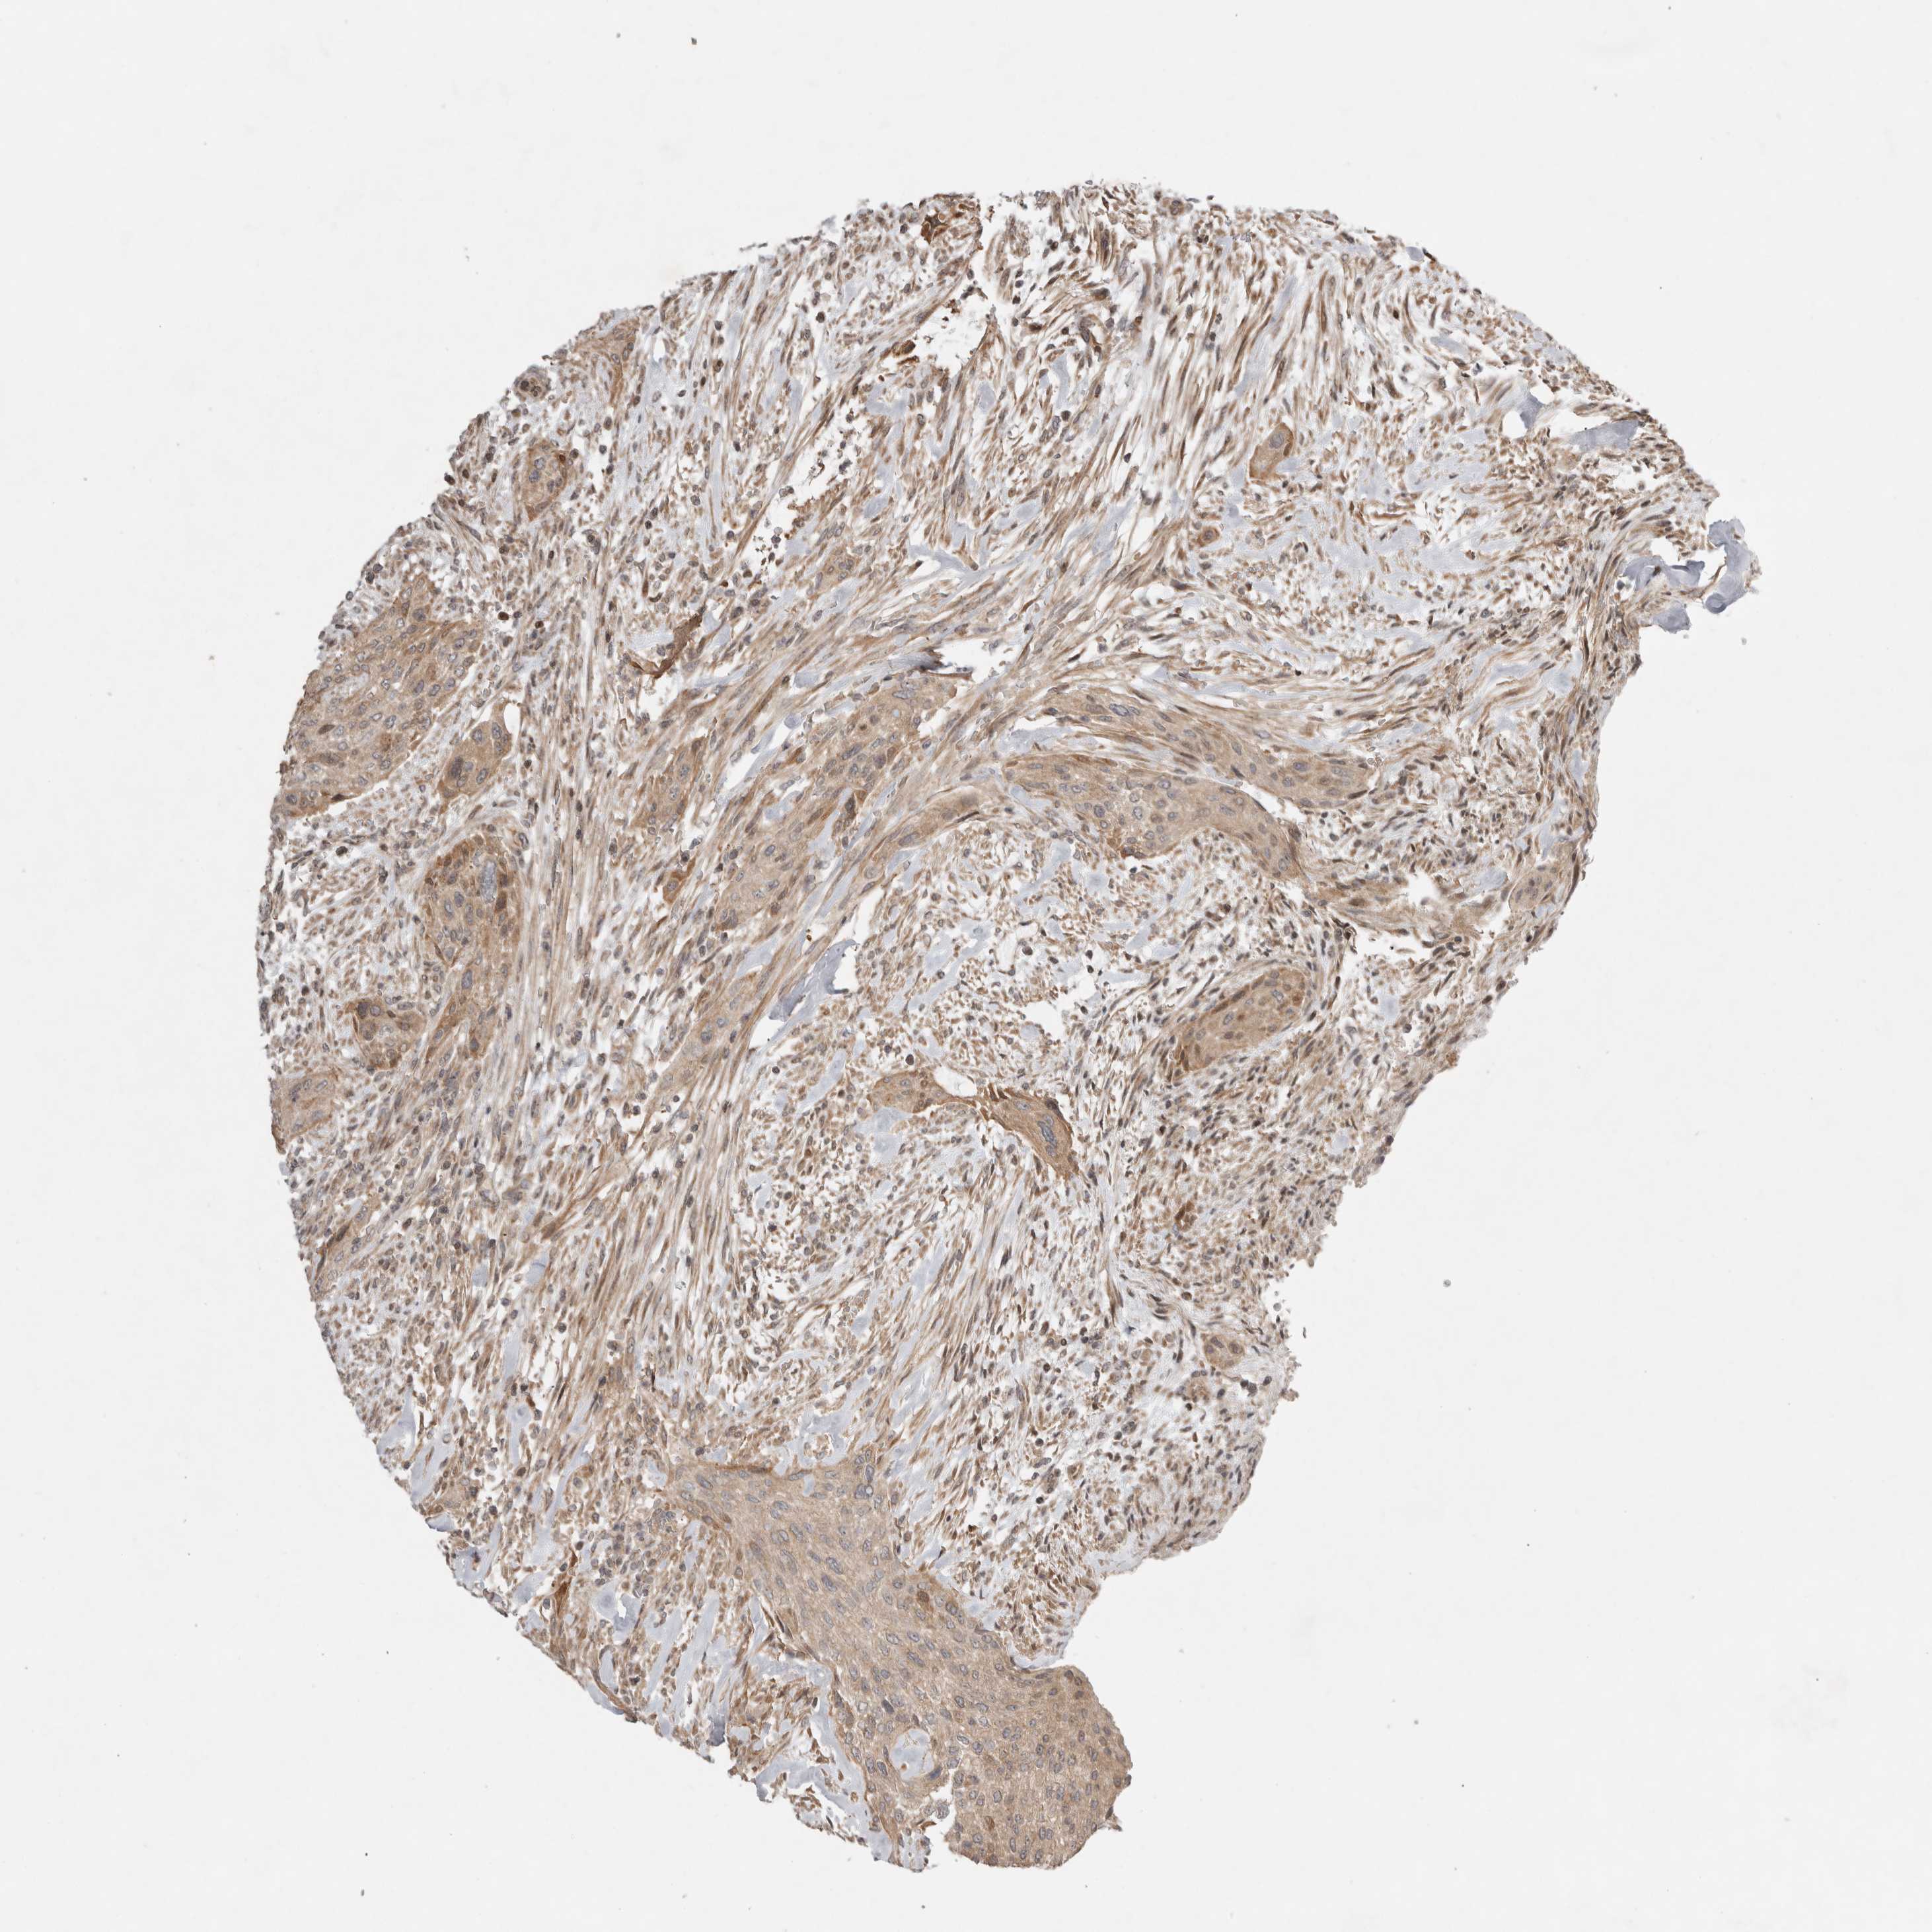

UROTHELIAL CANCER - Protein expressioni

A mouse-over function shows sample information and annotation data. Click on an image to view it in a full screen mode. Samples can be filtered based on level of antibody staining by selecting one or several of the following categories: high, medium, low and not detected. The assay and annotation is described here.

Antibody stainingi

Antibody staining in the annotated cell types in the current human tissue is reported as not detected, low, medium, or high, based on conventional immunohistochemistry profiling in selected tissues. This score is based on the combination of the staining intensity and fraction of stained cells.

Each image is clickable and will lead to virtual microscopy that enables deeper exploration of all samples and also displays staining intensity scores, fraction scores and subcellular localization as well as patient and tissue information for each sample.

Antibody HPA016496

Antibody CAB022082

Staining

High

Medium

Low

Not detected

Intensity

Strong

Moderate

Weak

Negative

Quantity

>75%

75%-25%

<25%

None

Location

Nuclear

Cytoplasmic/membranous

Cytoplasmic/membranous,nuclear

Urothelial carcinoma, Low grade

Urothelial carcinoma, High grade